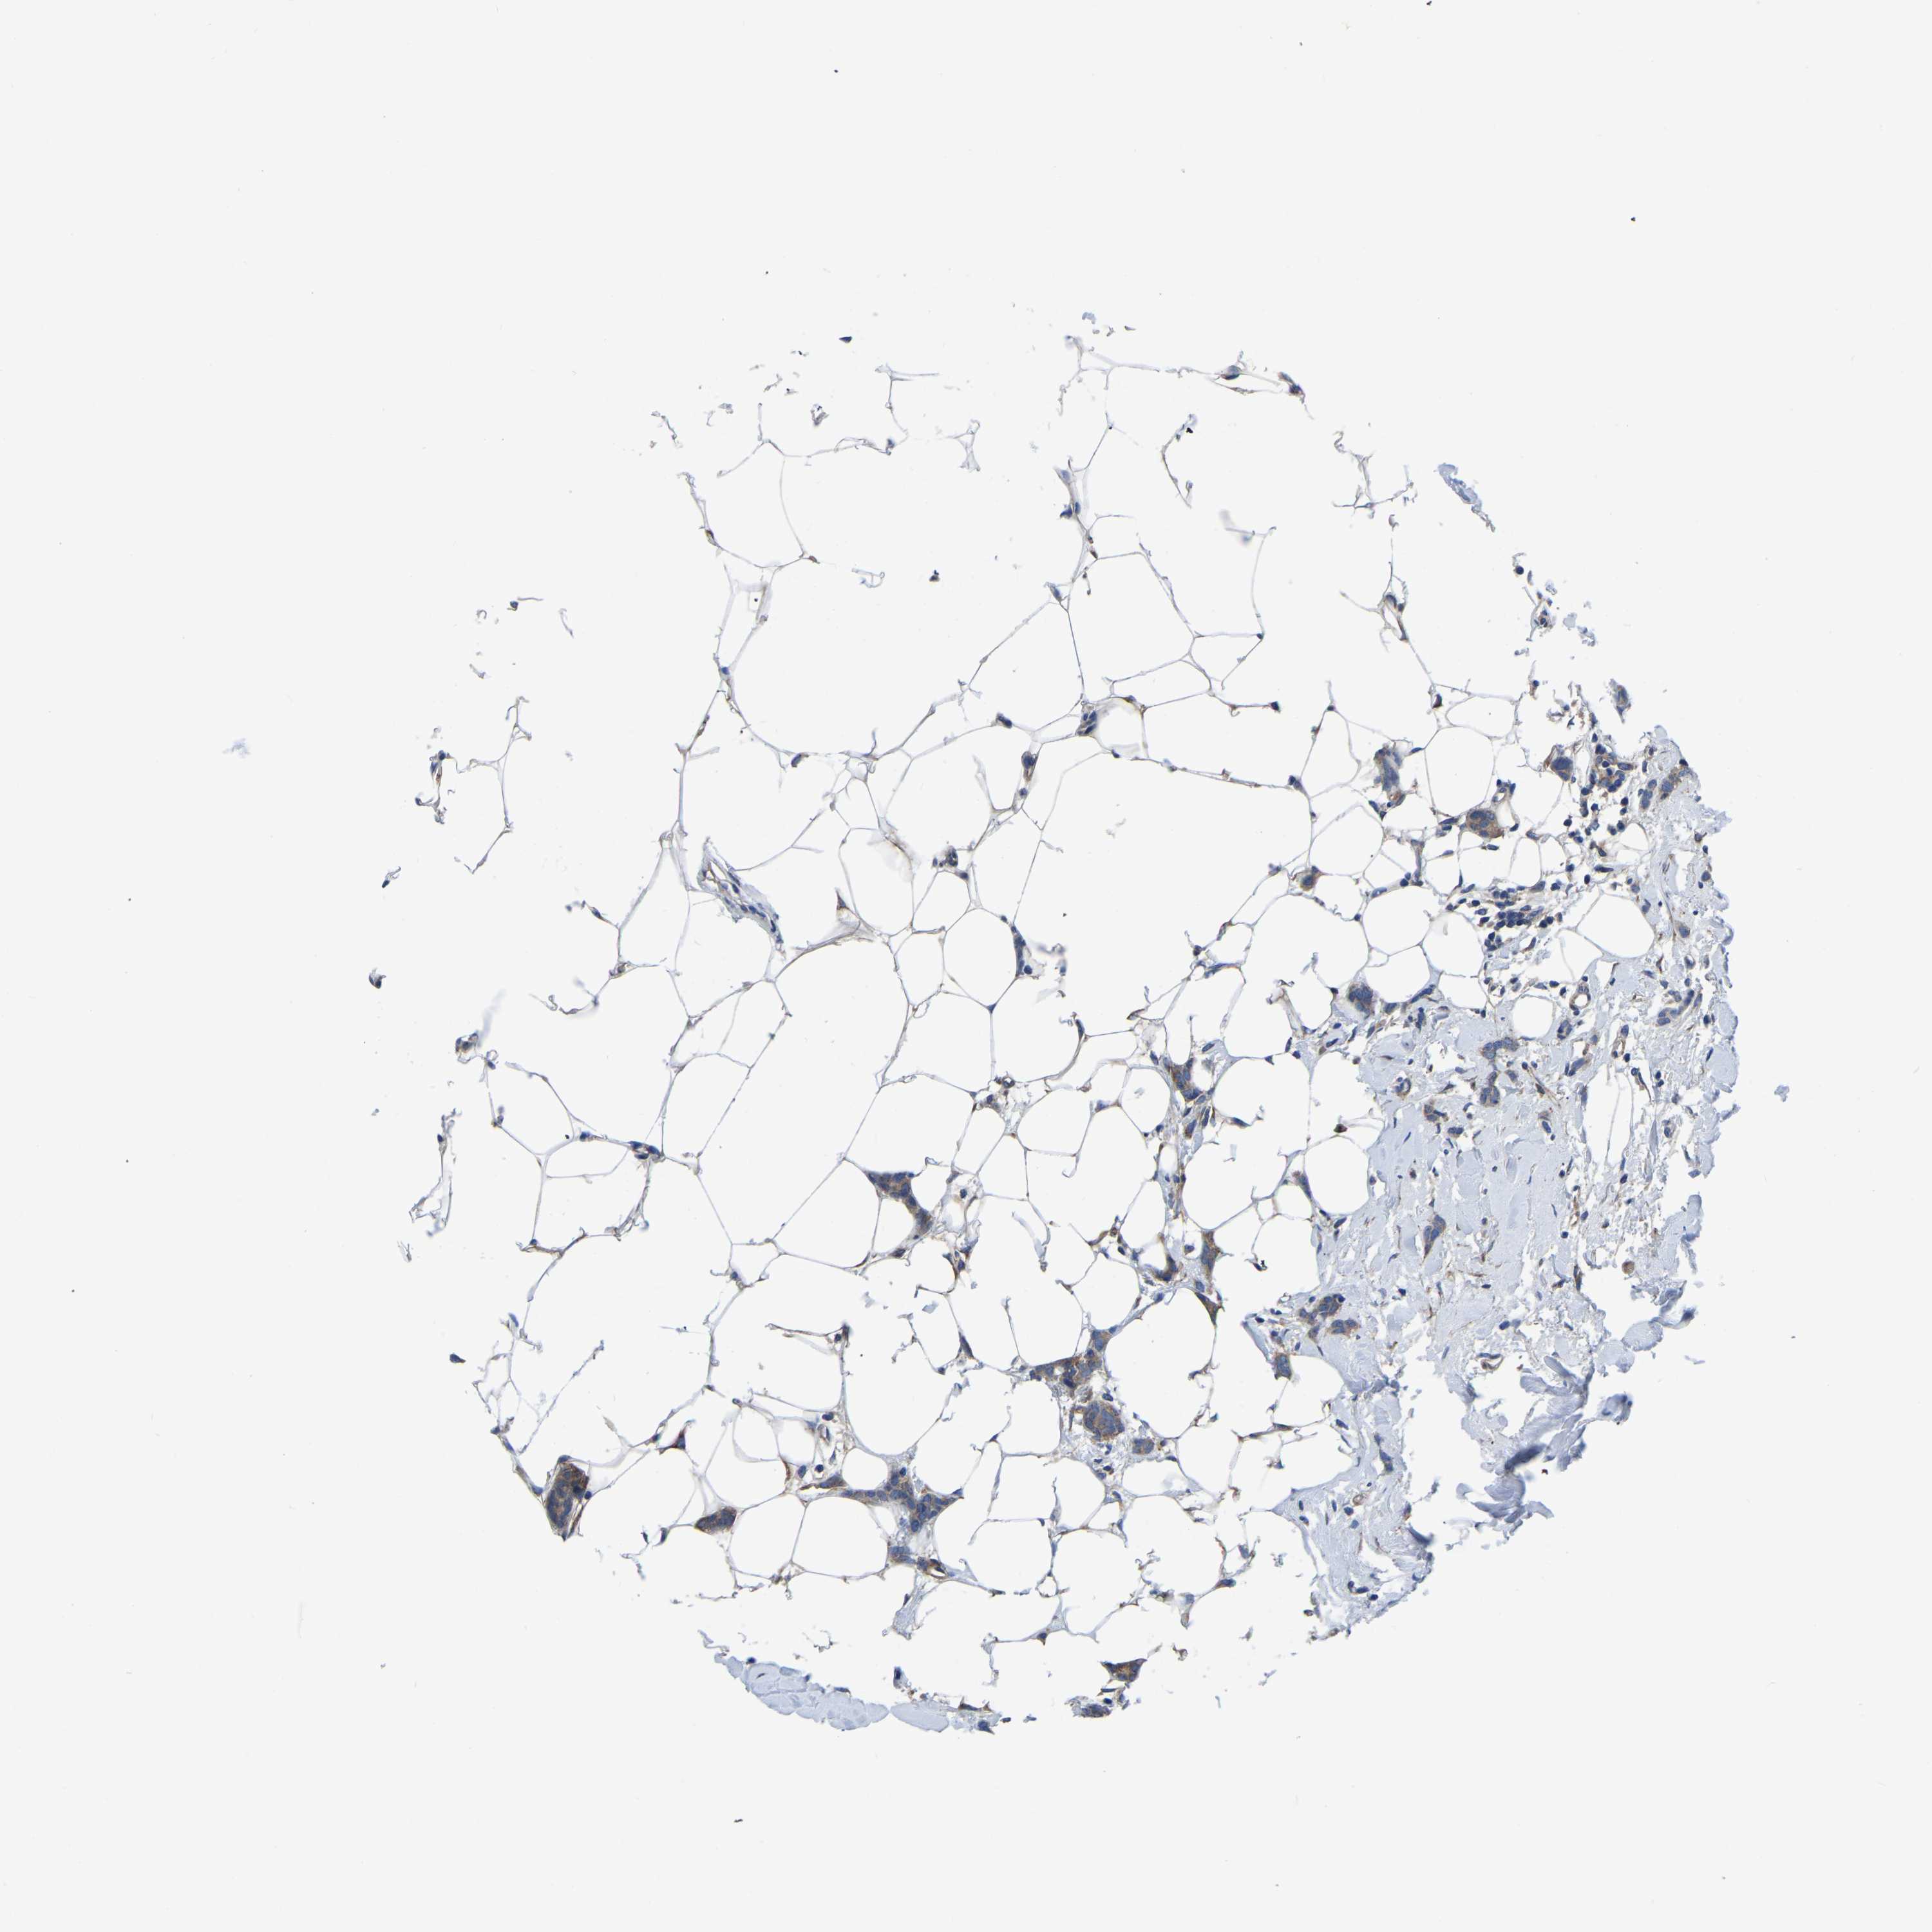

CANCER BREAST CANCER Show tissue menu

BRCA TCGA BRCA VALIDATION PROTEIN EXPRESSION

Breast cancer

Human cancer